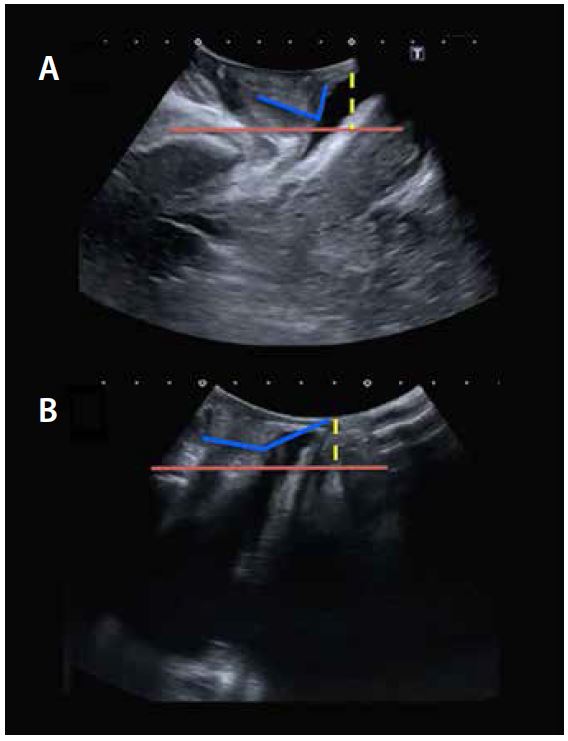

При ультразвуковій оцінці сіток проти нетримання сечі слід проводити дослідження різних параметрів, серед яких найбільш вивченим є розташування сітки відносно уретри та міра компресії уретральної сітки:

• Розташування слінга по відношенню до уретри: Вимірюють довжину проксимального відділу уретри, поділену на загальну довжину уретри. Цей параметр коливається від 0% до 100%. 0-процентильне значення вказує на те, що слінг знаходиться близько до шийки сечового міхура, а 100-процентильне значення вказує на те, що він знаходиться близько до зовнішнього проходу уретри. Оптимальне положення слінгу знаходиться між 40-м і 70-м процентилем (мал. 9A).

• Вимірювання компресії сітки уретри: найважливішим параметром є проміжок між слінгом та лобком. Визначається як відстань між центром слінга та заднім краєм лобкового симфізу. Чим більша відстань від слінгу до лобка, тим менше стиснення середини уретри та натяг слінгу (мал. 9B).

Малюнок 9. Розташування слінгу відносно уретри (Малюнок А, вгору). Слінгово-лобкова щілина (малюнок В вниз).